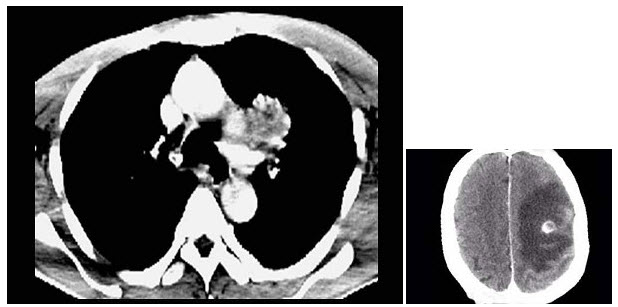

女,26岁,临床诊断为绒毛膜癌,行经腹子宫全切术后1月,CT检查如图所示,下列说法正确的是()

A.左肾周可见低密度区,增强后无强化,其内有散在的片状稍高密度影

B.双肾未见异常

C.考虑为左肾外伤性出血

D.考虑为绒毛膜癌肾转移

E.合并有左肾周自发性血肿